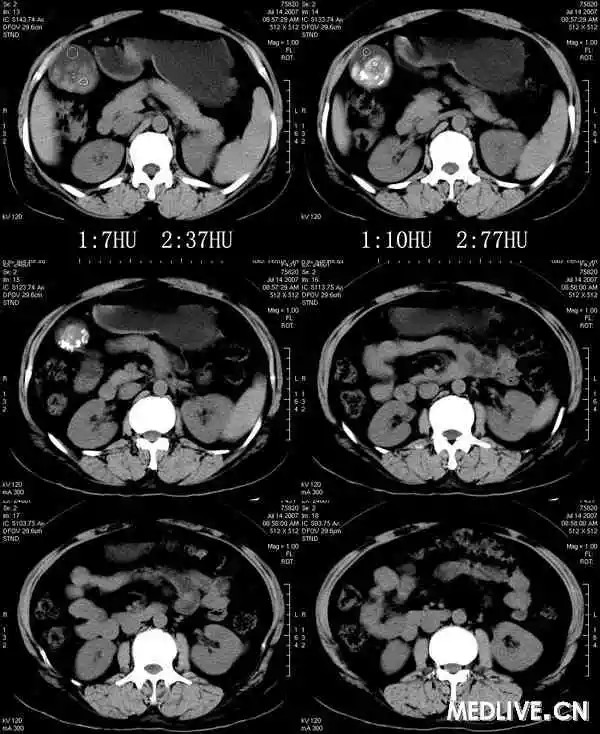

【影像表现】

胆囊内混杂高密度影,内有不规则形钙化,胆囊壁略增厚。

CT表现因结石化学成分不同,可为高密度、等密度、低密度、环状结石。等、低密度结石CT不易发现,胆影葡胺增强检查见胆囊内可移动的充盈缺损可明确。